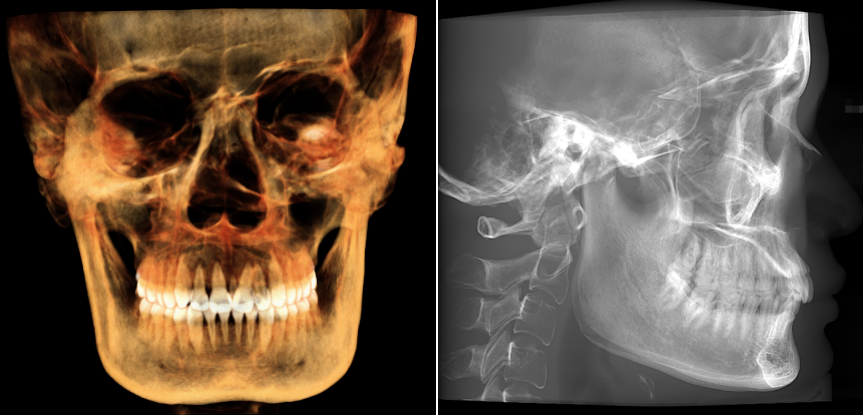

口腔设备有什么一文读懂 | 口腔影像设备大科普,哪种才是最适合你的选择?_https://www.jmylbn.com_新闻资讯_第13张

▲大视野图像

大视野可覆盖大部分头颅颌面,显示从上颌到下颌及双侧颞颌关节的完整形态适用于上下颌全牙列、颌面外科、全口种植以及正畸正颌等领域的临床应用。